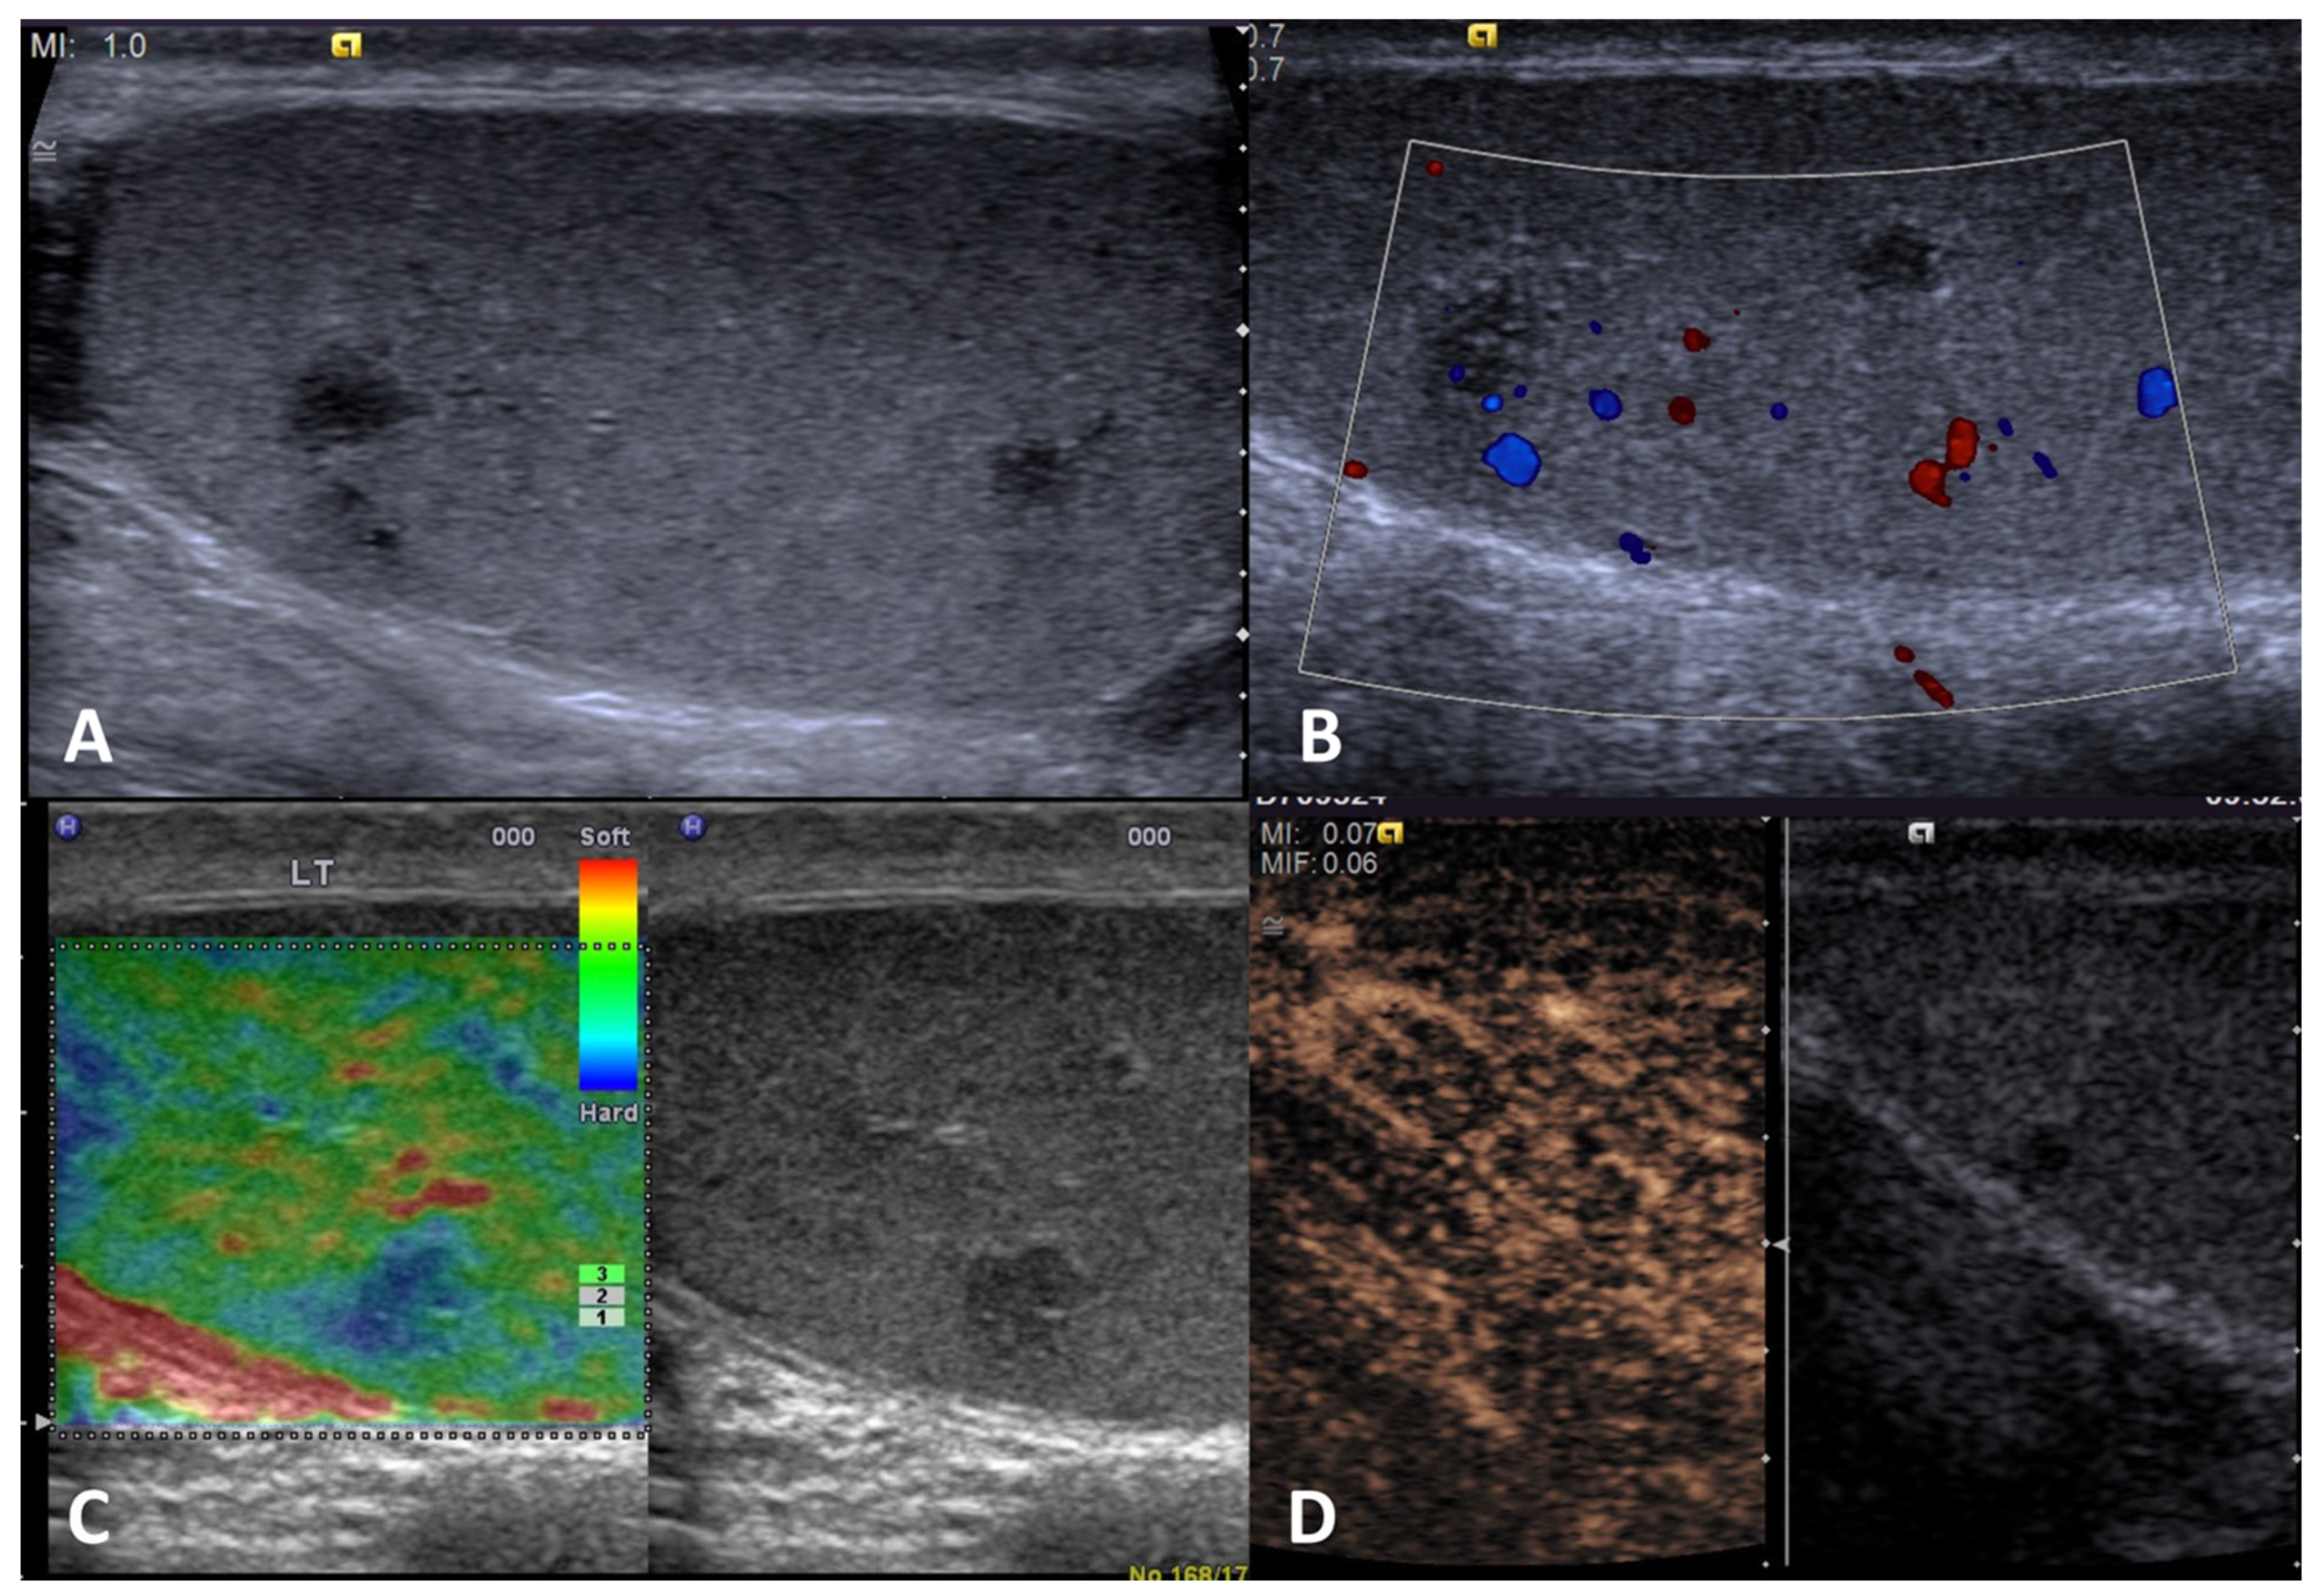

| Adrenal rest tumor | Patients with congenital adrenal hyperplasia; usually not palpable | Hypoechoic lesions with irregular margins, hyperechogenic foci, typically localized in the mediastinum testis, usually bilateral | Markedly vascularized | Hyperenhanced | Hard lesions with low/absent elastic strain |

4.3. Testicular Adrenal Rest Tumors (TARTs)